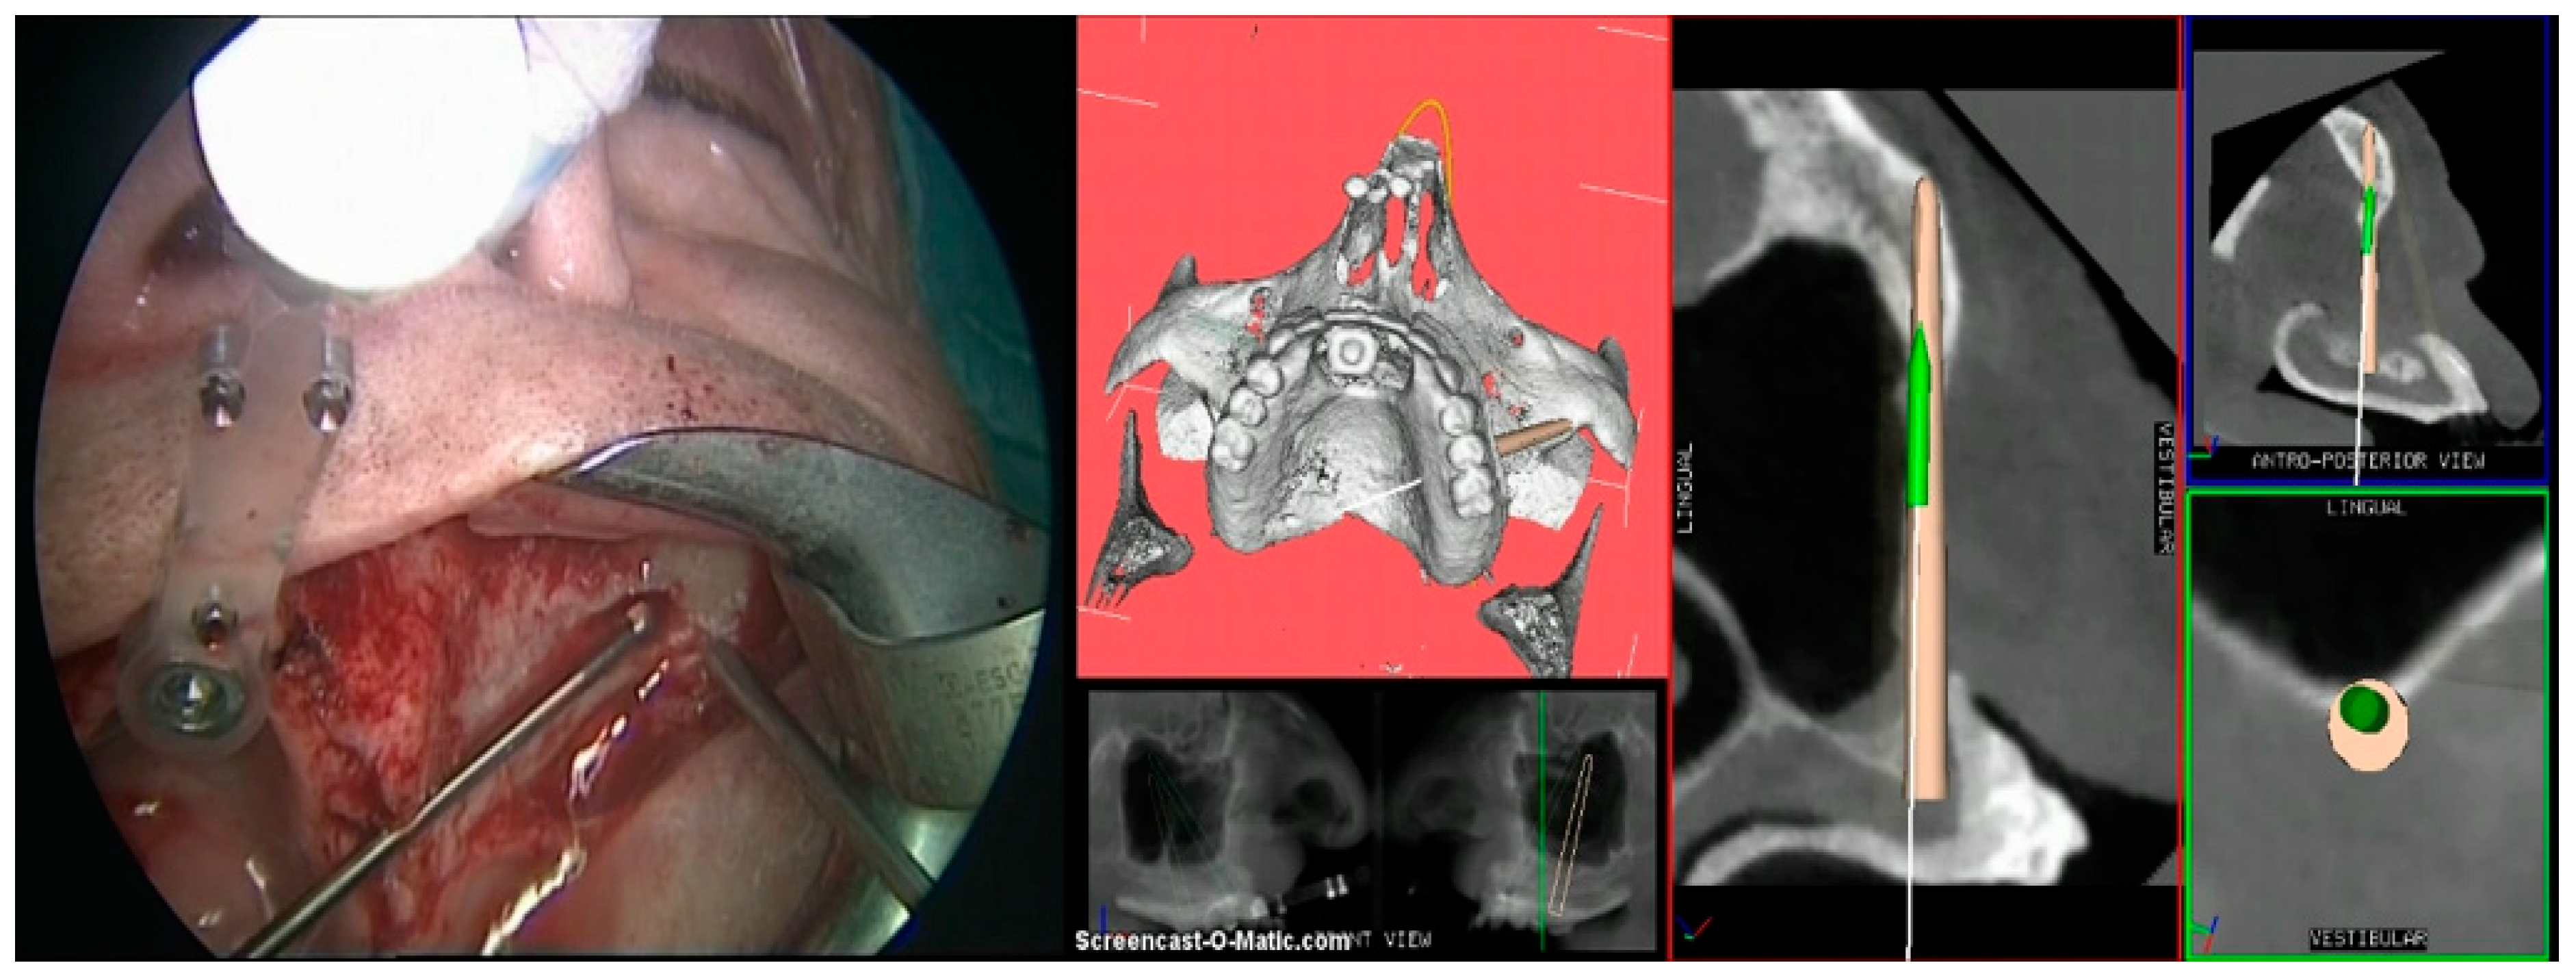

2. Case Report

3. Procedure

- Step 4. Surgery: navigation of the drill along the predefined surgical plan.